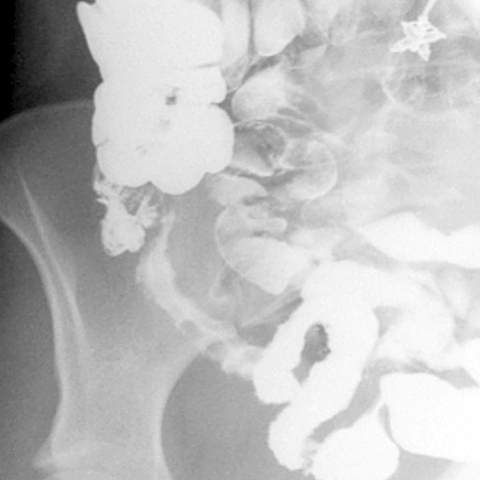

26 year-old female presents with chronic diarrhea, abdominal pain and weight loss. [2 of 2]